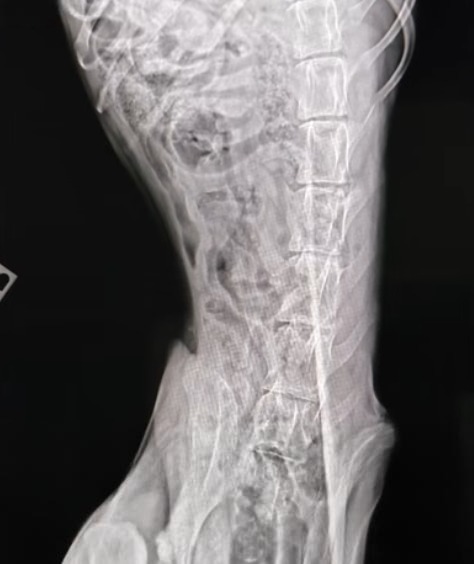

Doctors decided to move forward with surgery in hopes of saving his injured leg. The first operation was complex but successful. Everyone hoped it would be the beginning of his recovery.

Unfortunately, complications soon followed. His leg did not heal as expected, and infection became a concern. A second surgery was required to correct the problem.

When healing still did not improve, a third procedure became necessary. Each surgery tested his fragile body and the patience of the veterinary team.

At one point, doctors had to consider a painful possibility. If his leg could not heal, amputation might be the only option left to save his life.